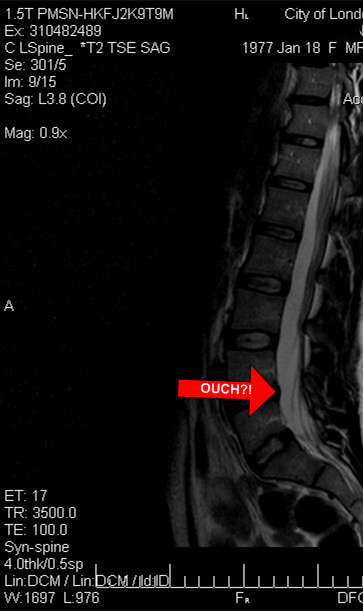

An MRI was suggested, so I once again benched myself, and I waited.

The radiologist's report claimed a normal result, which my sports med doc agreed with and suggested a few weeks of accupuncture. More than half of MRIs administered to people my age show disc issues that have no injury symptoms according to the doc, so it seems that a normal scan may just mean nothing extreme.

A few weeks in, I'm no better, and my physio, who is a spine specialist, is encouraging a second opinion because he and several of his colleagues think that the bump highlighted in the picture is the cause of my woes. That's where a disc appears to be pressing on my nerve.